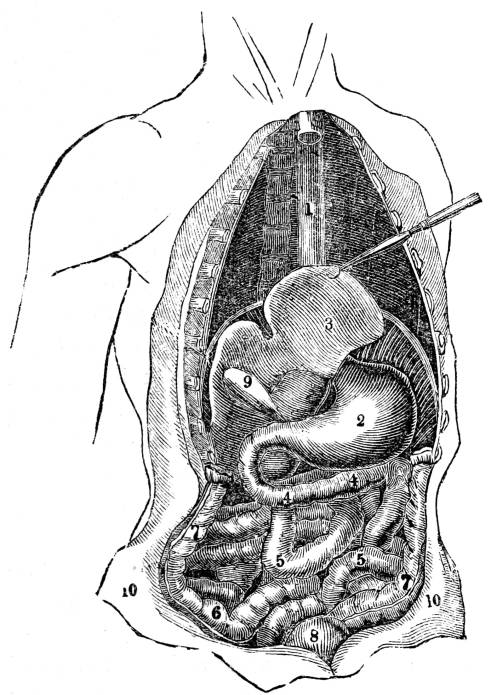

Fig. CXXXIV.—

View of the Respiratory Apparatus in

Man.

1. The Trachea. 2. The right lung. 3. The left lung.

4. Fissures, dividing each lung into, 5. Large portions

termed lobes. 6. Smaller divisions termed lobules. 7.

Pericardium. 8. Heart. 9. Aorta. 10. Diaphragm separating

the cavity of the thorax from that of the abdomen.

357. In man there are two pulmonary bags (fig.

CXXXIV. 2, 3), of nearly equal size, which, together

with the heart, completely fill the large cavity

of the thorax (fig. CXXXIV.), their external surface

being everywhere in immediate contact with

the thoracic walls. One of these bags is placed on

the right side of the body, constituting the right

lung (fig. CXXXIV. 2), and the other on the left,

constituting the left lung (fig. CXXXIV. 3). Each

lung is divided by deep fissures, into large portions

called lobes (figs. CXXXIV. 4, and CXXXV.

6), of which there are three belonging to the

right, and two to the left lung. Each lobe is

subdivided into innumerable smaller parts termed

lobules (figs. CXXXIV. 6, and CXXXV. 6), while the

lobules successively diminish in size until they

terminate in minute vesicles that constitute the

great bulk of the organ (fig. CXXXV. 8).